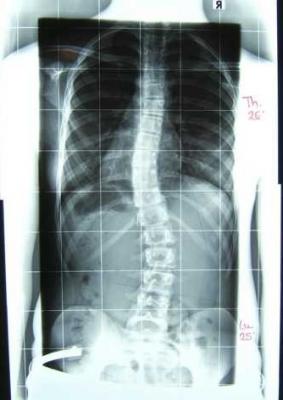

Hier sind Kokos Bilder!

Die Korrekturwerte sind wie folgt: Von lumbal 25° auf 10°, (60%),

von thorakal 26° auf 18°, (~30%),

neu dazugekommen, aber laut Herr Rahmouni zu vernachlässigen: hochthorakal 19°

Wir hatten um ein gut tragbares Korsett gebeten, das ist es auch geworden.

Wohl deshalb, und auch weil bei Koko die Skoliose genau anders herum gebogen ist wie in 95% der Fälle, sind die Werte nicht sooo toll...

Was meint ihr, muss da sofort mehr Druck drauf, und was ist das mit dem hochthorakalen Bogen, hat sich sowas bei euch auch im Korsett entwickelt?

forum_photo-röntgen ohne korsett.jpg

forum_photo-röntgen ohne korsett.jpg (16.9 KiB) 12997 mal betrachtet